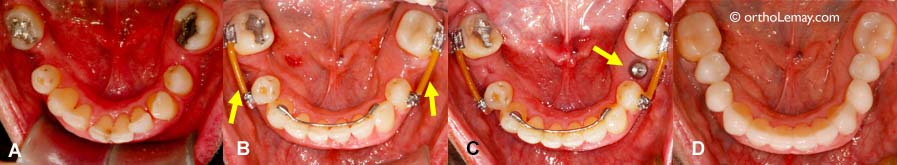

(A) Ce traitement orthodontique visait à replacer les dents inférieures dans le but de remplacer les dents manquantes à l’aide d’implants dentaires. Les dents ont été redressées et l’espace a été ouvert de façon optimale pour recevoir les implants. (B) À la fin de l’orthodontie, les appareils correcteurs (broches) ont été enlevés, sauf vis-à-vis les espaces où une section de fil (flèches) maintient les dents de chaque côté de l’espace afin qu’elles ne se déplacent pas en attendant la pose des implants et des couronnes. Une attelle de rétention fixe régulière maintient les dents antérieures en place. (C) Les implants ont été posés pendant la période de rétention. L’implant inférieur gauche est indiqué par la flèche. (D) Une fois les implants et couronnes posées, il n’est plus nécessaire de garder les sections de fil.